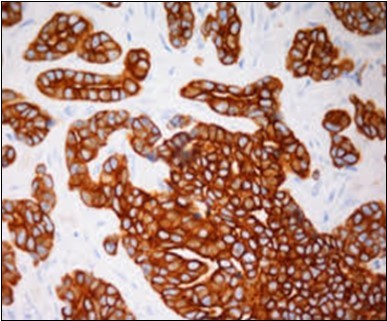

Granular arrangement of malignant cells and intercellular bridges are conspicuous with the demonstration of nuclear atypia, pleomorphism, prominent mitosis and tumour necrosis. A peripheral palisade is discernible within the cellular aggregates. Mitotic figures are common and can be quantified as up to 12 mitosis/ high power field. Tumour differentiation can prominently be of the ductal category with the demonstration of intra-cytoplasmic lumina. Comedo type tumour necrosis is evident along with foci of squamous differentiation The neoplasm is reactive to periodic acid Schiff ‘s (PAS) stain. (Figure 1, Figure 2, Figure 3, Figure 4, Figure 5, Figure 6, Figure 7, Figure 8, Figure 9, Figure 10, Figure 11, Figure 12, Figure 13.

Figure 1.Solid aggregates of tumour cells and duct structures in eccrine porocarcinoma (14).

Figure 2.Epidermal projections lined with atypical and malignant epithelial cells in eccrine porocarcinoma (14).

Figure 3.Cohesive accumulations with numerous ductular articulations of carcinoma cells in eccrine porocarcinoma (15).